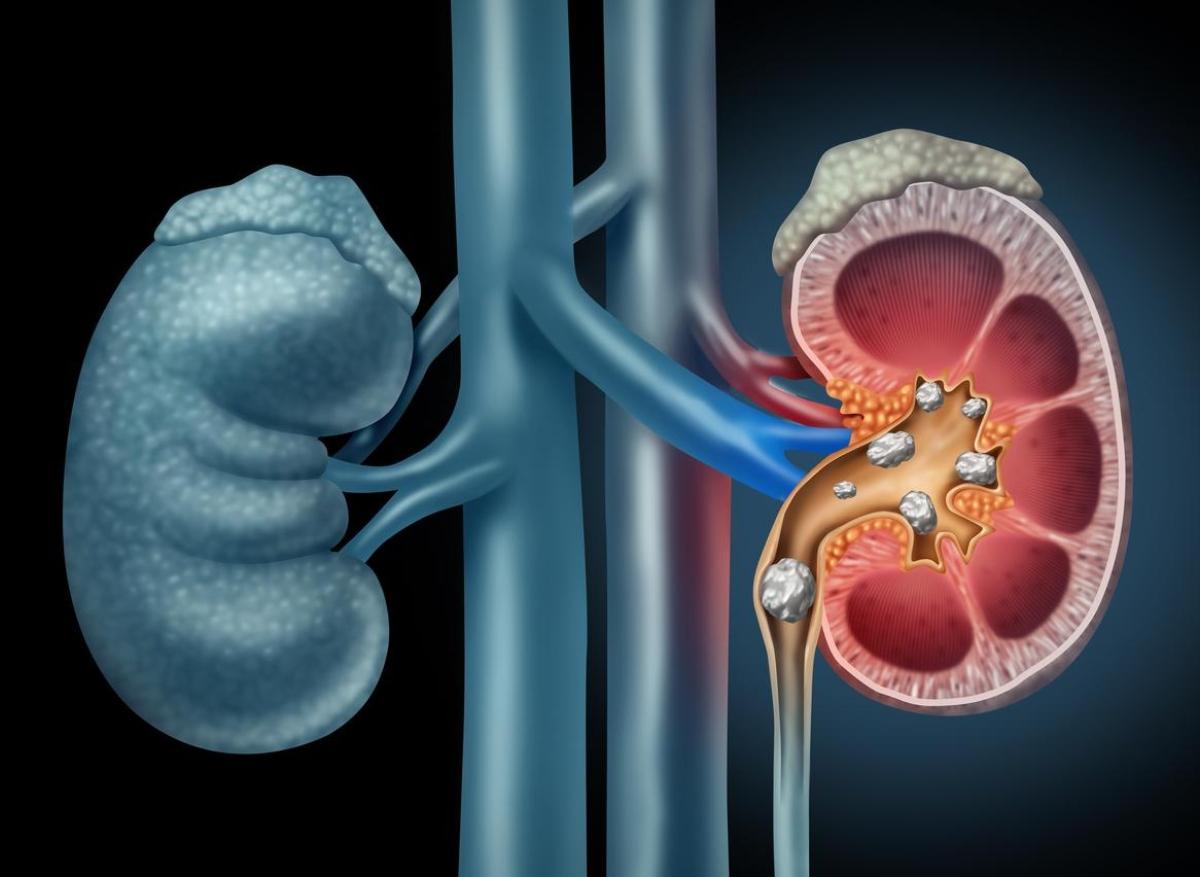

- Ben-Schonewille/istock

L'insuffisance rénale chronique touche plus de 6 millions de personnes en France. A ce jour, c'est une maladie incurable dont on peut juste ralentir l'évolution. Les podocytes, les cellules épithéliales du glomérule, régissent en temps normal la filtration rénale. Et ce sont ces cellules qui sont la plupart du temps détruites en cas d'insuffisance rénale.